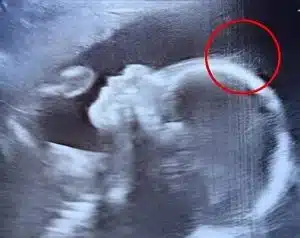

« Un instant… est-ce que ce serait… des cheveux ? », s’exclame-t-il, entre surprise et amusement. Un collègue rejoint alors la scène, et l’observation se poursuit sur un ton léger, évoquant le futur look de rockeur du bébé. À l’écran, de légers filaments dansent avec la fluidité du liquide amniotique, offrant un spectacle aussi rare que poétique.

L’équipe médicale rassure immédiatement Émilie : la pousse des cheveux in utero est un phénomène tout à fait normal. Ce qui sort de l’ordinaire, en revanche, c’est leur densité et la netteté avec laquelle ils apparaissent à l’image. Une telle visibilité à ce stade de la grossesse est peu commune.